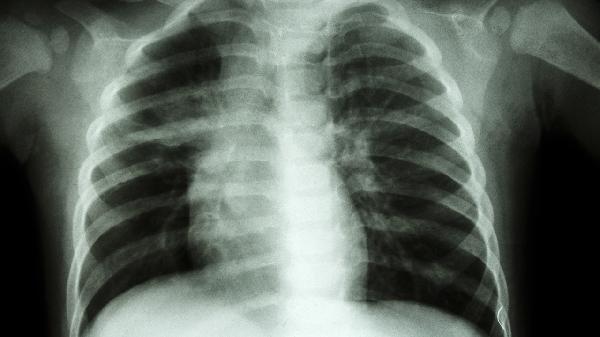

4、影像学检查:胸部X线或CT是诊断尘肺的主要手段,可显示肺部结节、纤维化等特征性改变。早期尘肺的影像学表现可能不明显,需结合职业史和临床症状综合判断。定期复查有助于监测病情变化,及时调整治疗方案。